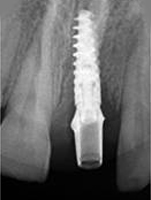

X-ray of Implant + Abutment

Single Tooth Implant